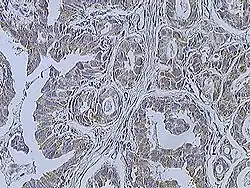

Histopathologic criteria

On microscopic evaluation carcinomatous cells are seen below the basement membrane of lactiferous ducts and invade into the surrounding breast stroma. Otherwise, there are no specific histologic characteristics, essentially making it a diagnosis of exclusion.[21] The histopathologic characteristics seen in these lesions are heterogenous. The cells of a lesion of invasive carcinoma NST may retain >70% ductal differentiation or appear completely undifferentiated. The tumor cells may be arranged in sheets, nests, cords, or singly distributed. They are pleomorphic (i.e., vary in size and shape). They usually have prominent nucleoli and multiple mitotic cells per magnified field of view, which are features generally consistent with cancerous cells. The surrounding non-ductal tissue, known as stroma, can range from none to abundant.[22][23]

Small inclusions of special features may be present within an invasive carcinoma NST tissue sample, but will be 'limited' (i.e. <10%). Carcinomas of mixed type will have a specialized pattern or lobular carcinoma in the majority (i.e. at least 50%) of the tumor and a non-specialized pattern in between 10 and 49% of the sample. Thus, such tumors will be called mixed invasive NST and special type or mixed invasive carcinoma NST and lobular carcinoma.[24]

Invasive ductal carcinoma, with occasional entrapped normal ducts (arrow) -

Histopathology of invasive ductal carcinoma of the breast representing a scirrhous growth. Core needle biopsy. Hematoxylin and eosin stain. -

Invasive ductal carcinoma of the breast. H&E stain.